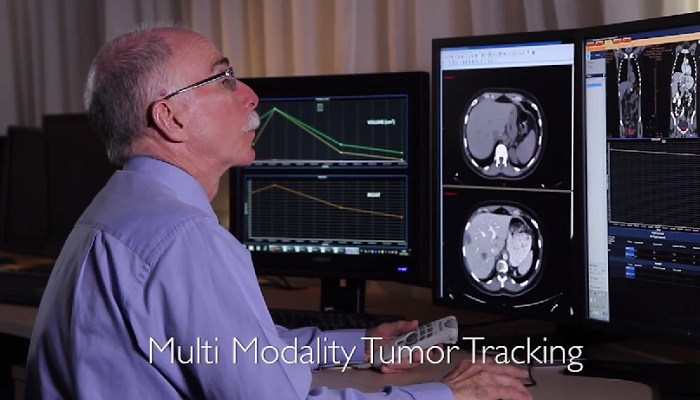

"باستخدام تقنيات التصوير المتقدمة من Philips مثل التصوير ثلاثي الأبعاد وعرض الشدة القصوى (MIP) وإعادة التشكيل متعدد الأسطح (MPR)، يمكننا الحصول على الصور بسهولة ومعالجتها لتحسين تشخيصنا. نحن نأخذ فكرة أفضل عن المستوى الذي وصل إليه المرض، كما يمكننا تقديم نصائح أفضل إلى الطبيب السريري حول ما يحدث." دكتور دارسي ليتل